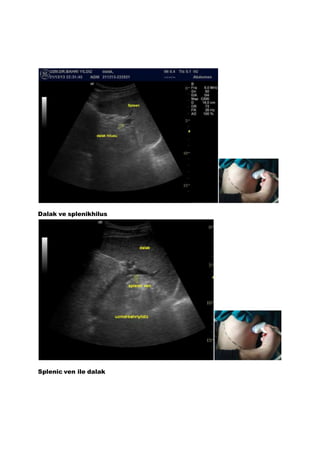

Dalak ve splenikhilus

Splenic ven ile dalak